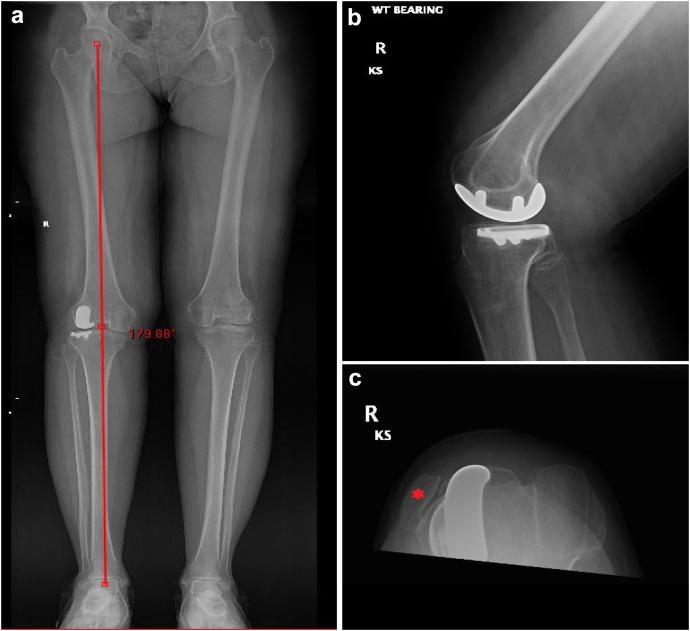

A 59-year-old woman with nail patella syndrome (NPS) presented with progressive and severe right knee pain for the past 3 years. Imaging demonstrated laterally dislocated patella, with asymmetric femoral trochlea, and advanced lateral compartment arthritis. The patient underwent robotic-assisted lateral unicompartmental knee arthroplasty (RAUKA). The patient saw marked improvements in patient-reported outcome measurements from her initial visit to the last follow-up visit. While treatment of knee osteoarthritis in patients with NPS can be difficult, especially with attempts of patellar realignment, we present a case of a patient who underwent RAUKA, with sustained improvements in patient outcomes and range of motion, at the 2-year follow-up visit. This study is the first of its kind to demonstrate the use of a novel technology in a rare condition.

一名59岁的指甲髌骨综合征(NPS)女性患者,在过去3年中出现进行性严重右膝疼痛。影像学检查显示髌骨外侧脱位,股骨滑车不对称,外侧间室关节炎进展。该患者接受了机器人辅助外侧单髁膝关节置换术(RAUKA)。从初次就诊到最后一次随访,患者报告的结局指标有显著改善。虽然NPS患者的膝骨关节炎治疗可能很困难,尤其是在尝试髌骨重新定位时,但我们介绍了一例接受RAUKA治疗的患者,在2年随访时患者结局和活动范围持续改善。本研究首次证明了在罕见疾病中使用新技术的情况。